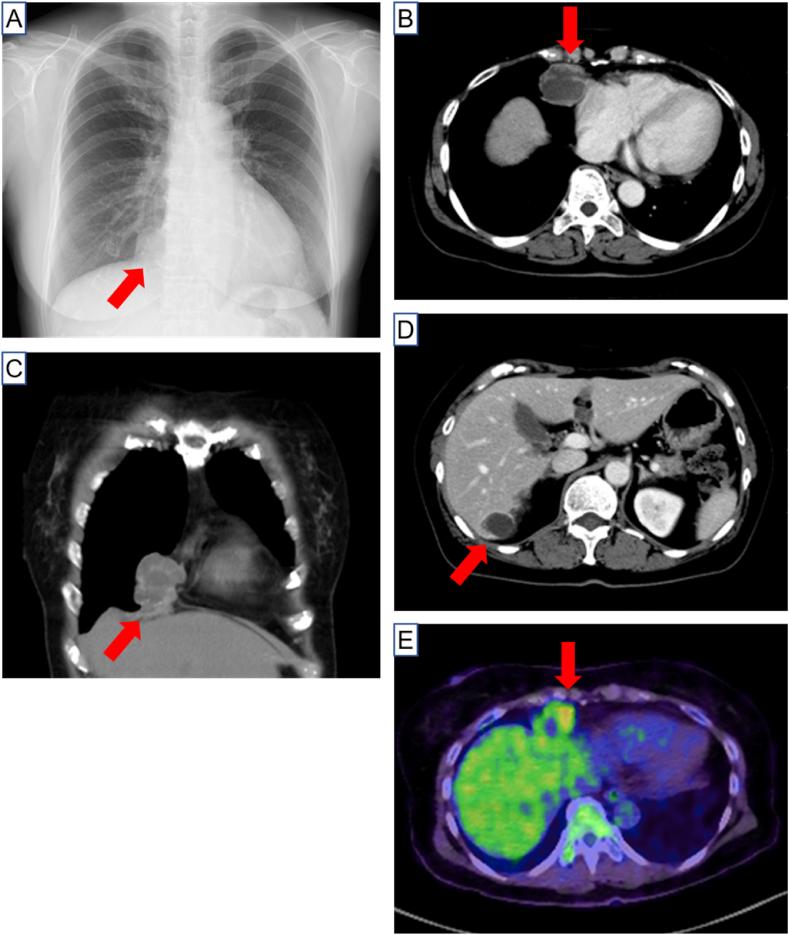

Mediastinal metastasis from ovarian serous carcinoma 29 years after initial treatment.

Ovarian cancer is a critically lethal gynecologic malignancy. More than 80% of patients with ovarian cancer have relapses within 5 years after initial treatment. However, recurrence from ovarian cancer more than 20 years later is extremely rare. We report a case of a 67-year-old female with mediastinal metastasis from ovarian cancer 29 years after initial gynecologic surgery and chemotherapy.